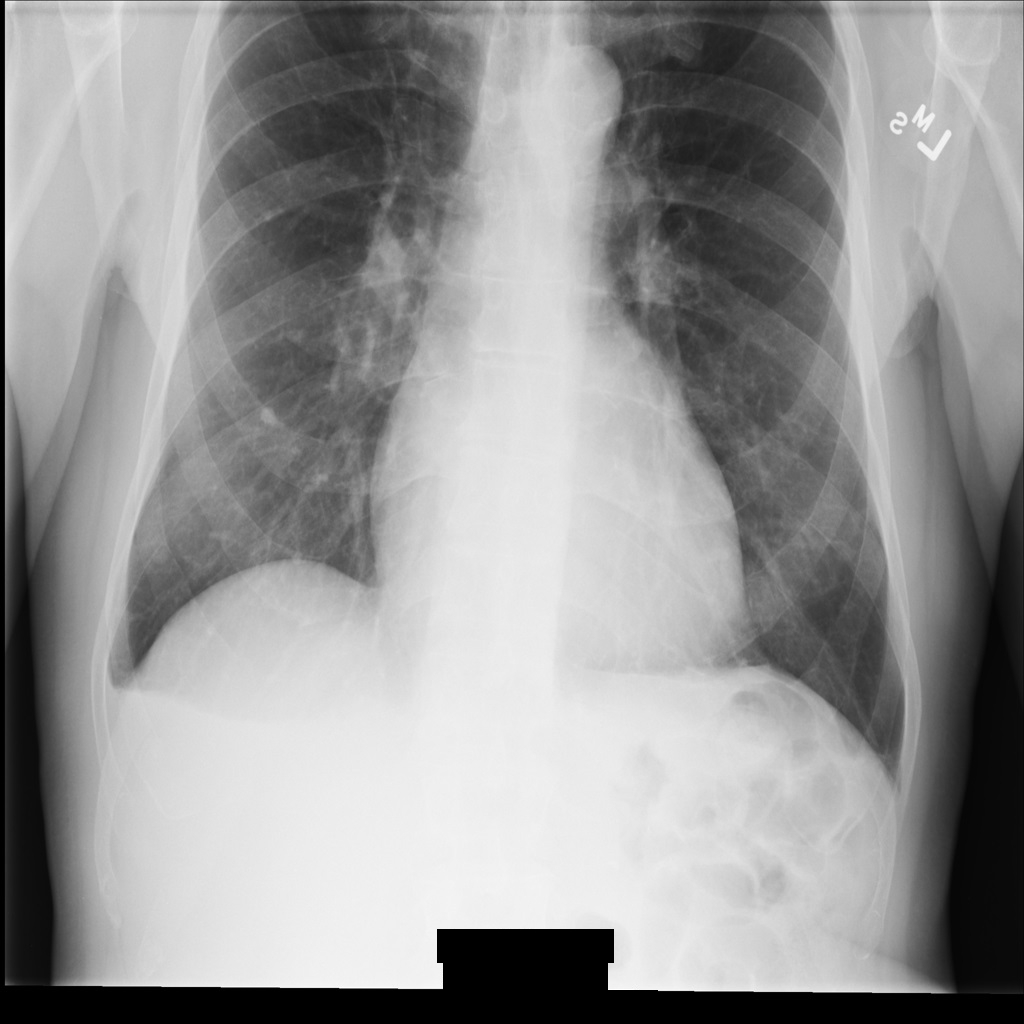

After de-identifying the image using REDACT_SENSITIVE_TEXT_CLEAN_DESCRIPTORS, the image looks like this. Notice that not all the burned-in text at the bottom of the image has been redacted. The text Female is still shown, because PatientSex (0010,0040) isn't one of the default DICOM infoTypes.

Figure 2. The DICOM instance after de-identification using REDACT_SENSITIVE_TEXT_CLEAN_DESCRIPTORS.